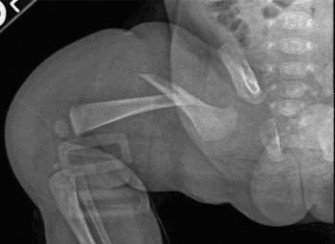

Step-by-Step Surgical Technique and Intervention

For the purpose of this Grand Rounds, let us detail the application of a one-and-a-half hip spica cast, which remains a fundamental skill for every orthopedic trauma and pediatric surgeon.

Reduction and Casting Technique

The fracture is reduced by applying longitudinal traction. In a proximal third fracture, the proximal fragment is flexed, abducted, and externally rotated by the iliopsoas and gluteal muscles. Therefore, we must bring the distal limb into a matching position of 90 degrees of hip flexion, 30-45 degrees of abduction, and mild external rotation. This is the classic "90-90" position.

We apply the cast material (typically a hybrid of plaster for the initial molding layers, followed by fiberglass for structural integrity). The cast extends from the nipple line down to the toes on the affected side, and down to the knee on the contralateral side (hence, a "one-and-a-half" spica).

The Art of Molding

The critical step is the mold. The surgeon must apply a gentle, broad-based supracondylar mold to control rotation and a lateral mold to prevent varus bowing. We must also ensure the cast is molded well around the iliac crests to prevent the cast from pistoning distally. Once the material sets, the abdominal towel is removed. The perineal opening is carefully trimmed and petaled with waterproof tape to allow for hygienic diapering. A post-application radiograph is obtained in the operating room to confirm acceptable alignment.